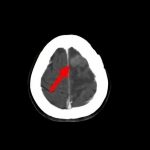

断層撮影

手術前2